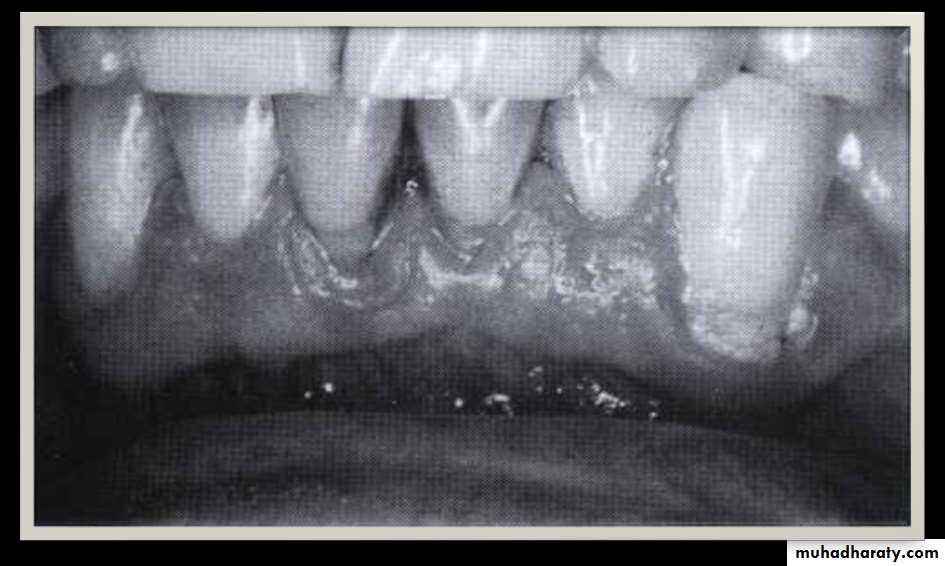

• Periodontal pockets around lower anterior teeth, showing rolled margins, edematous inflammatory changes and abundant calculus

• Signs And Symptoms

• Color changes

• Bluish-red marginal gingiva

• Bluish-red vertical zone

• extending from the gingival

• margin to the attached gingiva,a "rolled" edge separating the gingival margin from the tooth surface

• The presence

• of bleeding,

• suppuration, and loose, extruded

• teeth may also denote the presence of pockets